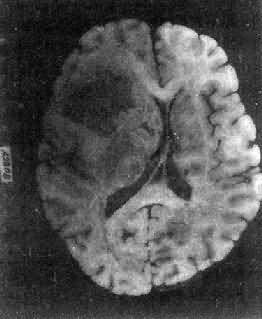

高度恶性的星形胶质细胞瘤称为多形性胶质母细胞瘤(glioblastoma multiforme),多见于成人。肿瘤好发于额叶、颞叶白质,浸润范围广,常可穿过胼胝体到对侧,呈蝴蝶状生长(图16-24)。瘤体因常有出血坏死而呈红褐色。镜下,细胞密集,异型性明显,可见怪异的单核或多核瘤巨细胞。出血坏死明显,是其区别于间变性星形胶质细胞瘤的特征。毛细血管明显增生,内皮细胞增生、肿大,可导致管腔闭塞和血栓形成。肿瘤发展迅速,预后极差,患者多在2年内死亡。

图16-24 多形性胶质母细胞瘤

在两半球内肿瘤呈蝴蝶状,边界不清,切面见有出血、坏死及液化